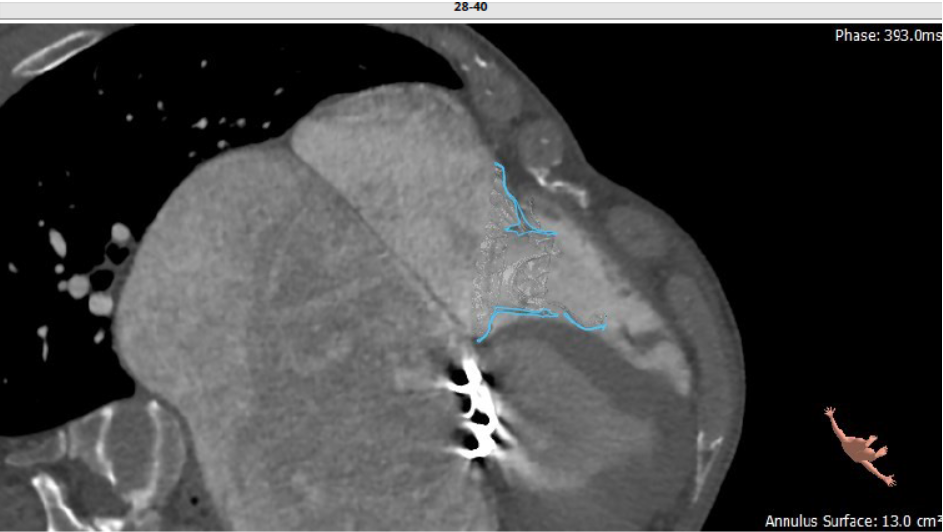

第二例患者为56岁男性,25年前接受了“主动脉瓣+二尖瓣机械瓣置换术”,约18年前出现三尖瓣关闭不全,近年来复查彩超示三尖瓣反流逐渐加重伴轻微黄疸、双下肢水肿,虽长期服用利尿剂治疗,但效果越来越差。长海医院心外科徐志云、陆方林团队综合该患者CT、超声检查结果,对该患者的情况进行了充分的评估和讨论,决定采用LuX-Valve®瓣膜系统对患者进行微创治疗。手术于7月12日下午进行,由于病人左心房扩大压迫右心房,心室游离壁距离瓣环中心仅29.8mm,再加上室间隔与瓣环夹角过大,手术操作有一定难度,瓣膜锚定也需要相当的经验。

根据术前CT的测量结果,选择使用JS/TTVI-28-40型号的LuX-Valve®瓣膜。陆方林教授用导管顺利将介入瓣送入右心室,过三尖瓣瓣环到达右心室,精准地控制着输送系统,最终和超声确认无瓣周漏后对瓣膜进行锚定,术后超声和造影显示瓣膜位置良好,几乎无反流。